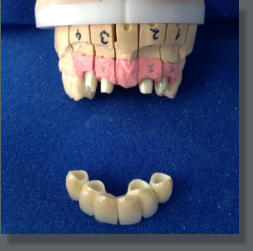

In unserer Praxis bieten wir Ihnen das gesamte Spektrum der verschiedenen Zahnersatzversorgungen an. Sowohl schon jahrzehntelang bewährte Versorgungen, als auch modernste Formen von Zahnersatz können für Sie realisiert werden. Man unterscheidet festsitzenden (Kronen, Brücken…) und herausnehmbaren (Teil-, Totalprothesen…) Zahnersatz. Dieser soll die Funktion (Kauen, Sprechen…) und die Ästhetik des Kausystems wiederherstellen. Unsere Partner in Sachen „Zahntechnik“ entnehmen Sie bitte der Rubrik „Links“. Folgende Zahnersatzleistungen können wir Ihnen anbieten: • Teilkronen (aus Metall oder Keramik) • Kronen und Brücken (aus Metall, mit Keramik verblendet oder aus Vollkeramik) • Klammerprothesen • Teleskopprothesen • Totalprothesen • Implantatgetragener Zahnersatz (festsitzend oder herausnehmbar) • etc.